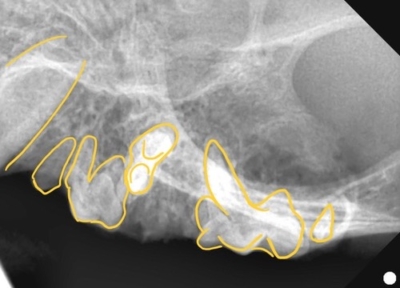

そして歯科レントゲン撮影を行いました。

なにがなにやらわからないと思い、黄色ラインで歯をなぞりました。右上顎です。中央に過剰な歯があり、回転して生えています。

右上顎も同様に中央に回転して生えている過剰歯があります。